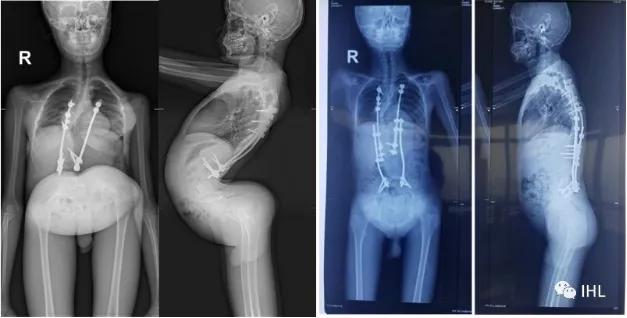

左边X片是Roye教授第一次看到孩子时的情况,而右边是Roye教授为孩子重新手术返修后的X片!

手术后孩子长高了近10公分,并且很快就可以下地行走了。